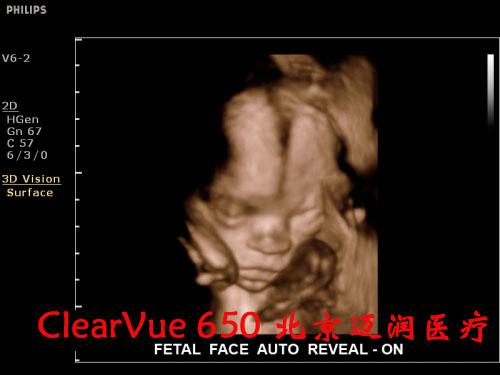

對實時三維功能而言,CV650是飛利浦CV系列產(chǎn)品“維時代”的開端。

良好的二維成像技術(shù)是保證實時三維圖像質(zhì)量的關(guān)鍵。CV650的實時三維成像融合了飛利浦傳統(tǒng)的優(yōu)勢技術(shù)SONOCT和Xres,保證了良好的圖像分辨力和對比度;另外,容積探頭也采用了“雙A探頭技術(shù)”,能夠?qū)崿F(xiàn)原始信號的零損耗,使呈現(xiàn)的三維圖像效果更逼真。同時,高速的處理內(nèi)核能使容積探頭實現(xiàn)最大48幁/秒的掃描速率,完成一次靜態(tài)掃描的時間也只需要2秒鐘,這些都保證了容積成像的可操作性。

在實時三維應(yīng)用上,CV650配備了胎兒面部自動識別軟件,全新的胎兒面部信息數(shù)字鑒定技術(shù),能夠一鍵清除遮擋物,使胎兒面部結(jié)構(gòu)尤其是異常缺陷能夠瞬間清晰顯示,大大便捷了醫(yī)生對胎兒面部的掃查過程。鑒于基層醫(yī)院對于胎兒心臟先天性疾病診斷能力的不足,這款機器還配備有STIC成像功能,簡單的操作、快速的圖像獲取、強大的離線分析能夠保證準確高效地獲取胎心不同標準切面,是基層超聲醫(yī)生診斷胎兒先心病的利器。

飛利浦ClearVue 650超聲系統(tǒng)臨床高清圖片